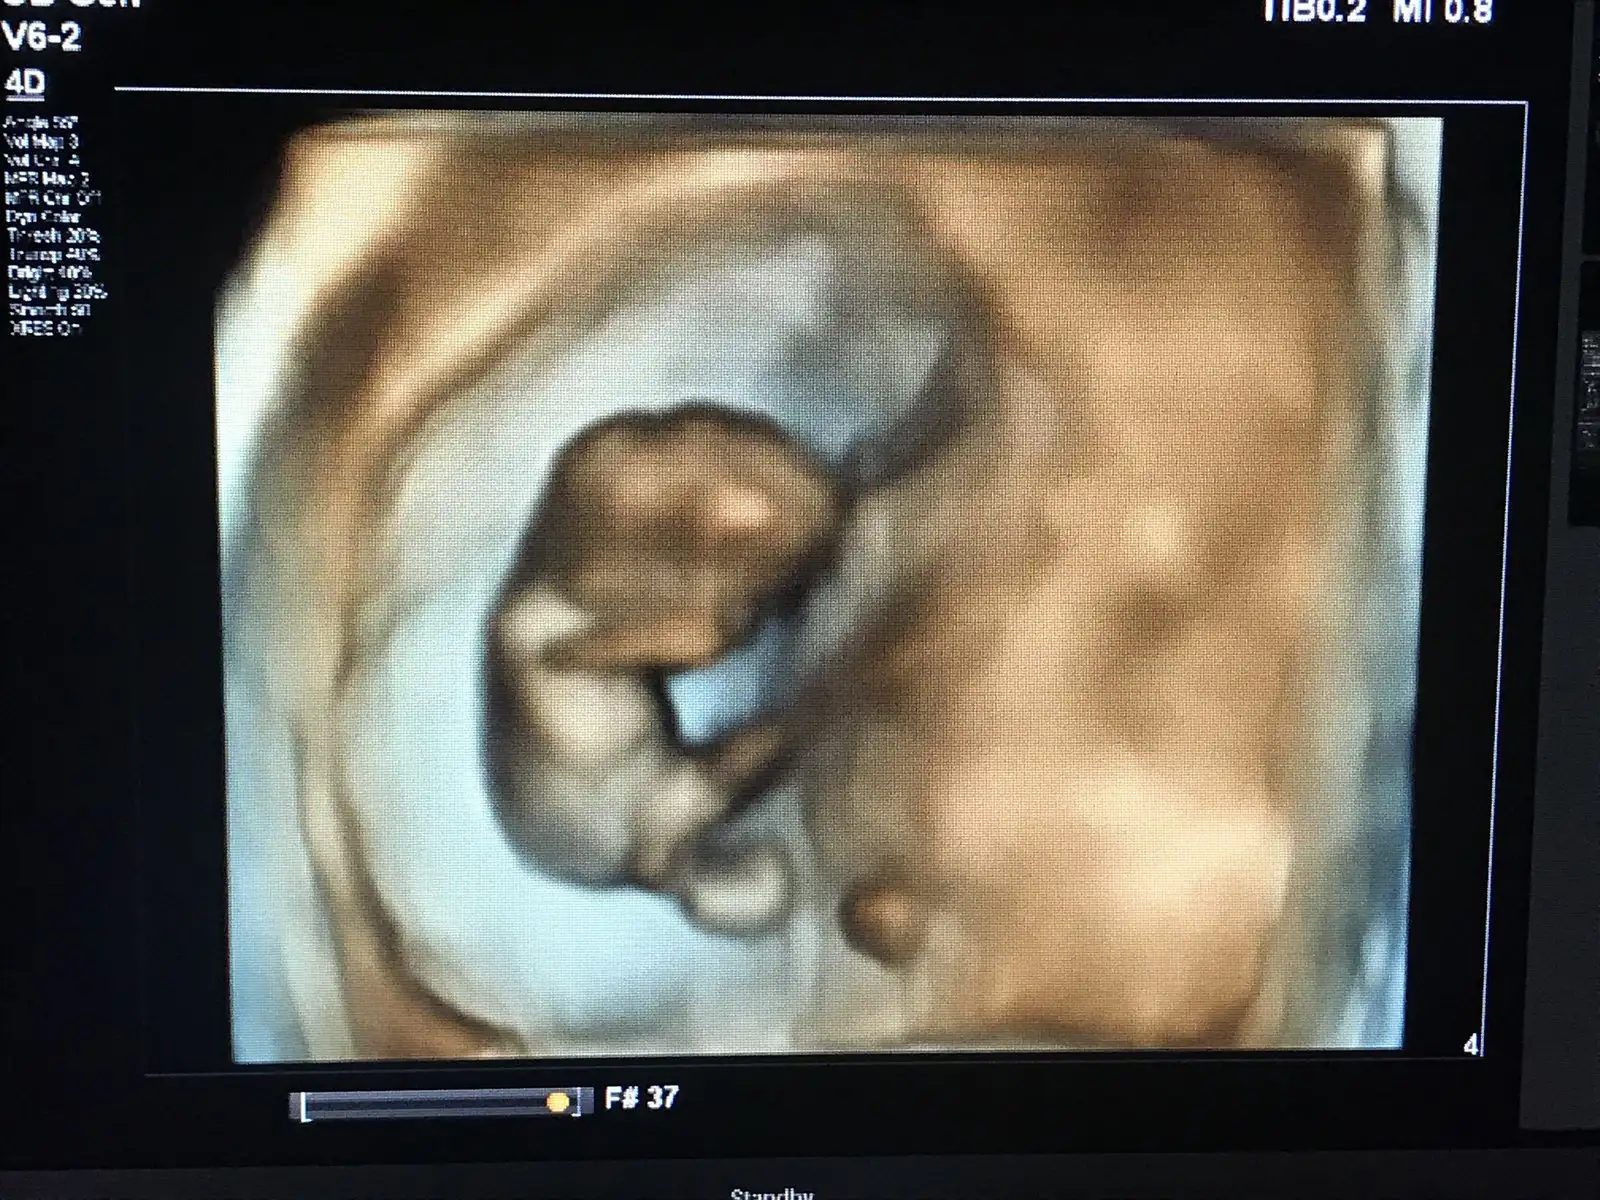

maşallah canım bu 3 boyutlu fotoları özelde mi veriyorlar devlette yokmu kiGeçen hafta cuma 10+1 haftalıkken yavrummmm

Doktorun süpriz yaptı heryeri belli artık renklide bakalım dedi ben tabi şok oldum heyecan yaptım o ara hiç beklemiyordum benim özelde ki doktorum yaptı devlette var mı bilmiyorum canımmaşallah canım bu 3 boyutlu fotoları özelde mi veriyorlar devlette yokmu ki

yaa ne güzel böyle daha bi minnoş çıkıyorlar benim eşim de bakıyo bakıyo anlamıyo hiç bi şeyDoktorun süpriz yaptı heryeri belli artık renklide bakalım dedi ben tabi şok oldum heyecan yaptım o ara hiç beklemiyordum benim özelde ki doktorum yaptı devlette var mı bilmiyorum canım